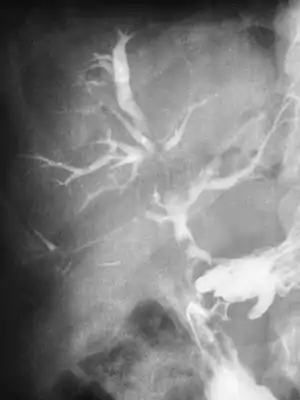

Diagnosis includes abdominal ultrasounds. A wide range of symptoms makes the diagnosis of biloma difficult. Delayed diagnosis 77% of patients resulted from abdominal bile collections and bile leaks after a laparoscopic cholecystectomy.[1] Radiographic imaging is used to diagnose and confirm bile leaks. Imaging also determines if it is extrahepatic or intrahepatic. A radiographic image will also show to what extent the bile leak is. A computerized tomography (CT) is also used to diagnose biloma. CT scans will show fluid collection in the right upper quadrant of the abdomen.In order to localize the leak, CT intravenous cholangiography can be used to show the communication between the biliary tree and the biloma. Magnetic resonance imaging (MRI) will demonstrate signaling intensity on T1-weighted imaging, and signaling intensity on T2-weighted imaging.[9] This means that there is a fluid build up.[9]